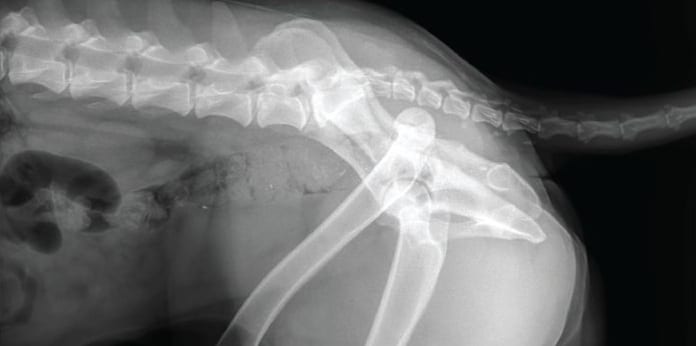

Fractures can be diagnosed in two different ways. The first thing is to see with the eyes. Vets have the experience and can tell which bone is fractured by looking. If the fracture is incomplete and the bone is not seen, imaging technology and radiology are used to take X-rays of the injured area. The CT scans will tell the right bone and fracture type in the dogs to provide the relevant treatment.

The most common bones that get fractures or cracks are the thigh bone, called the femur. Tibia and fibula also have a high percentage of fractures. The radius and ulna are the front leg bones that also get damaged. The pelvis bone and jaw are also among the top bones at high risk of getting fractures in dogs. Ribs and tail are at less risk compared to other bones in the body.